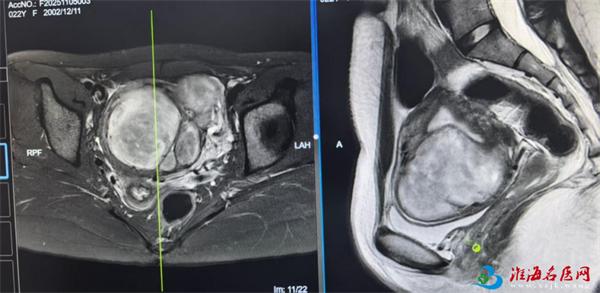

近日,徐州市妇幼保健院妇科十五区肿瘤亚专科蔡莉主任团队接诊到一名子宫肌瘤患者,术中竟从其体内取出30多枚子宫肌瘤,腹腔镜画面触目惊心!更令人震惊的是——这位22岁的患者不仅未婚,竟连性生活史都没有!

当腹腔镜下看到子宫的那一刻,连从业多年的蔡主任都倒吸冷气:密密麻麻的肌瘤如同葡萄串般挤满子宫!这场持续2小时的微创手术,成功拆除埋在花季少女体内的"定时炸弹"。

患者核磁 影 像